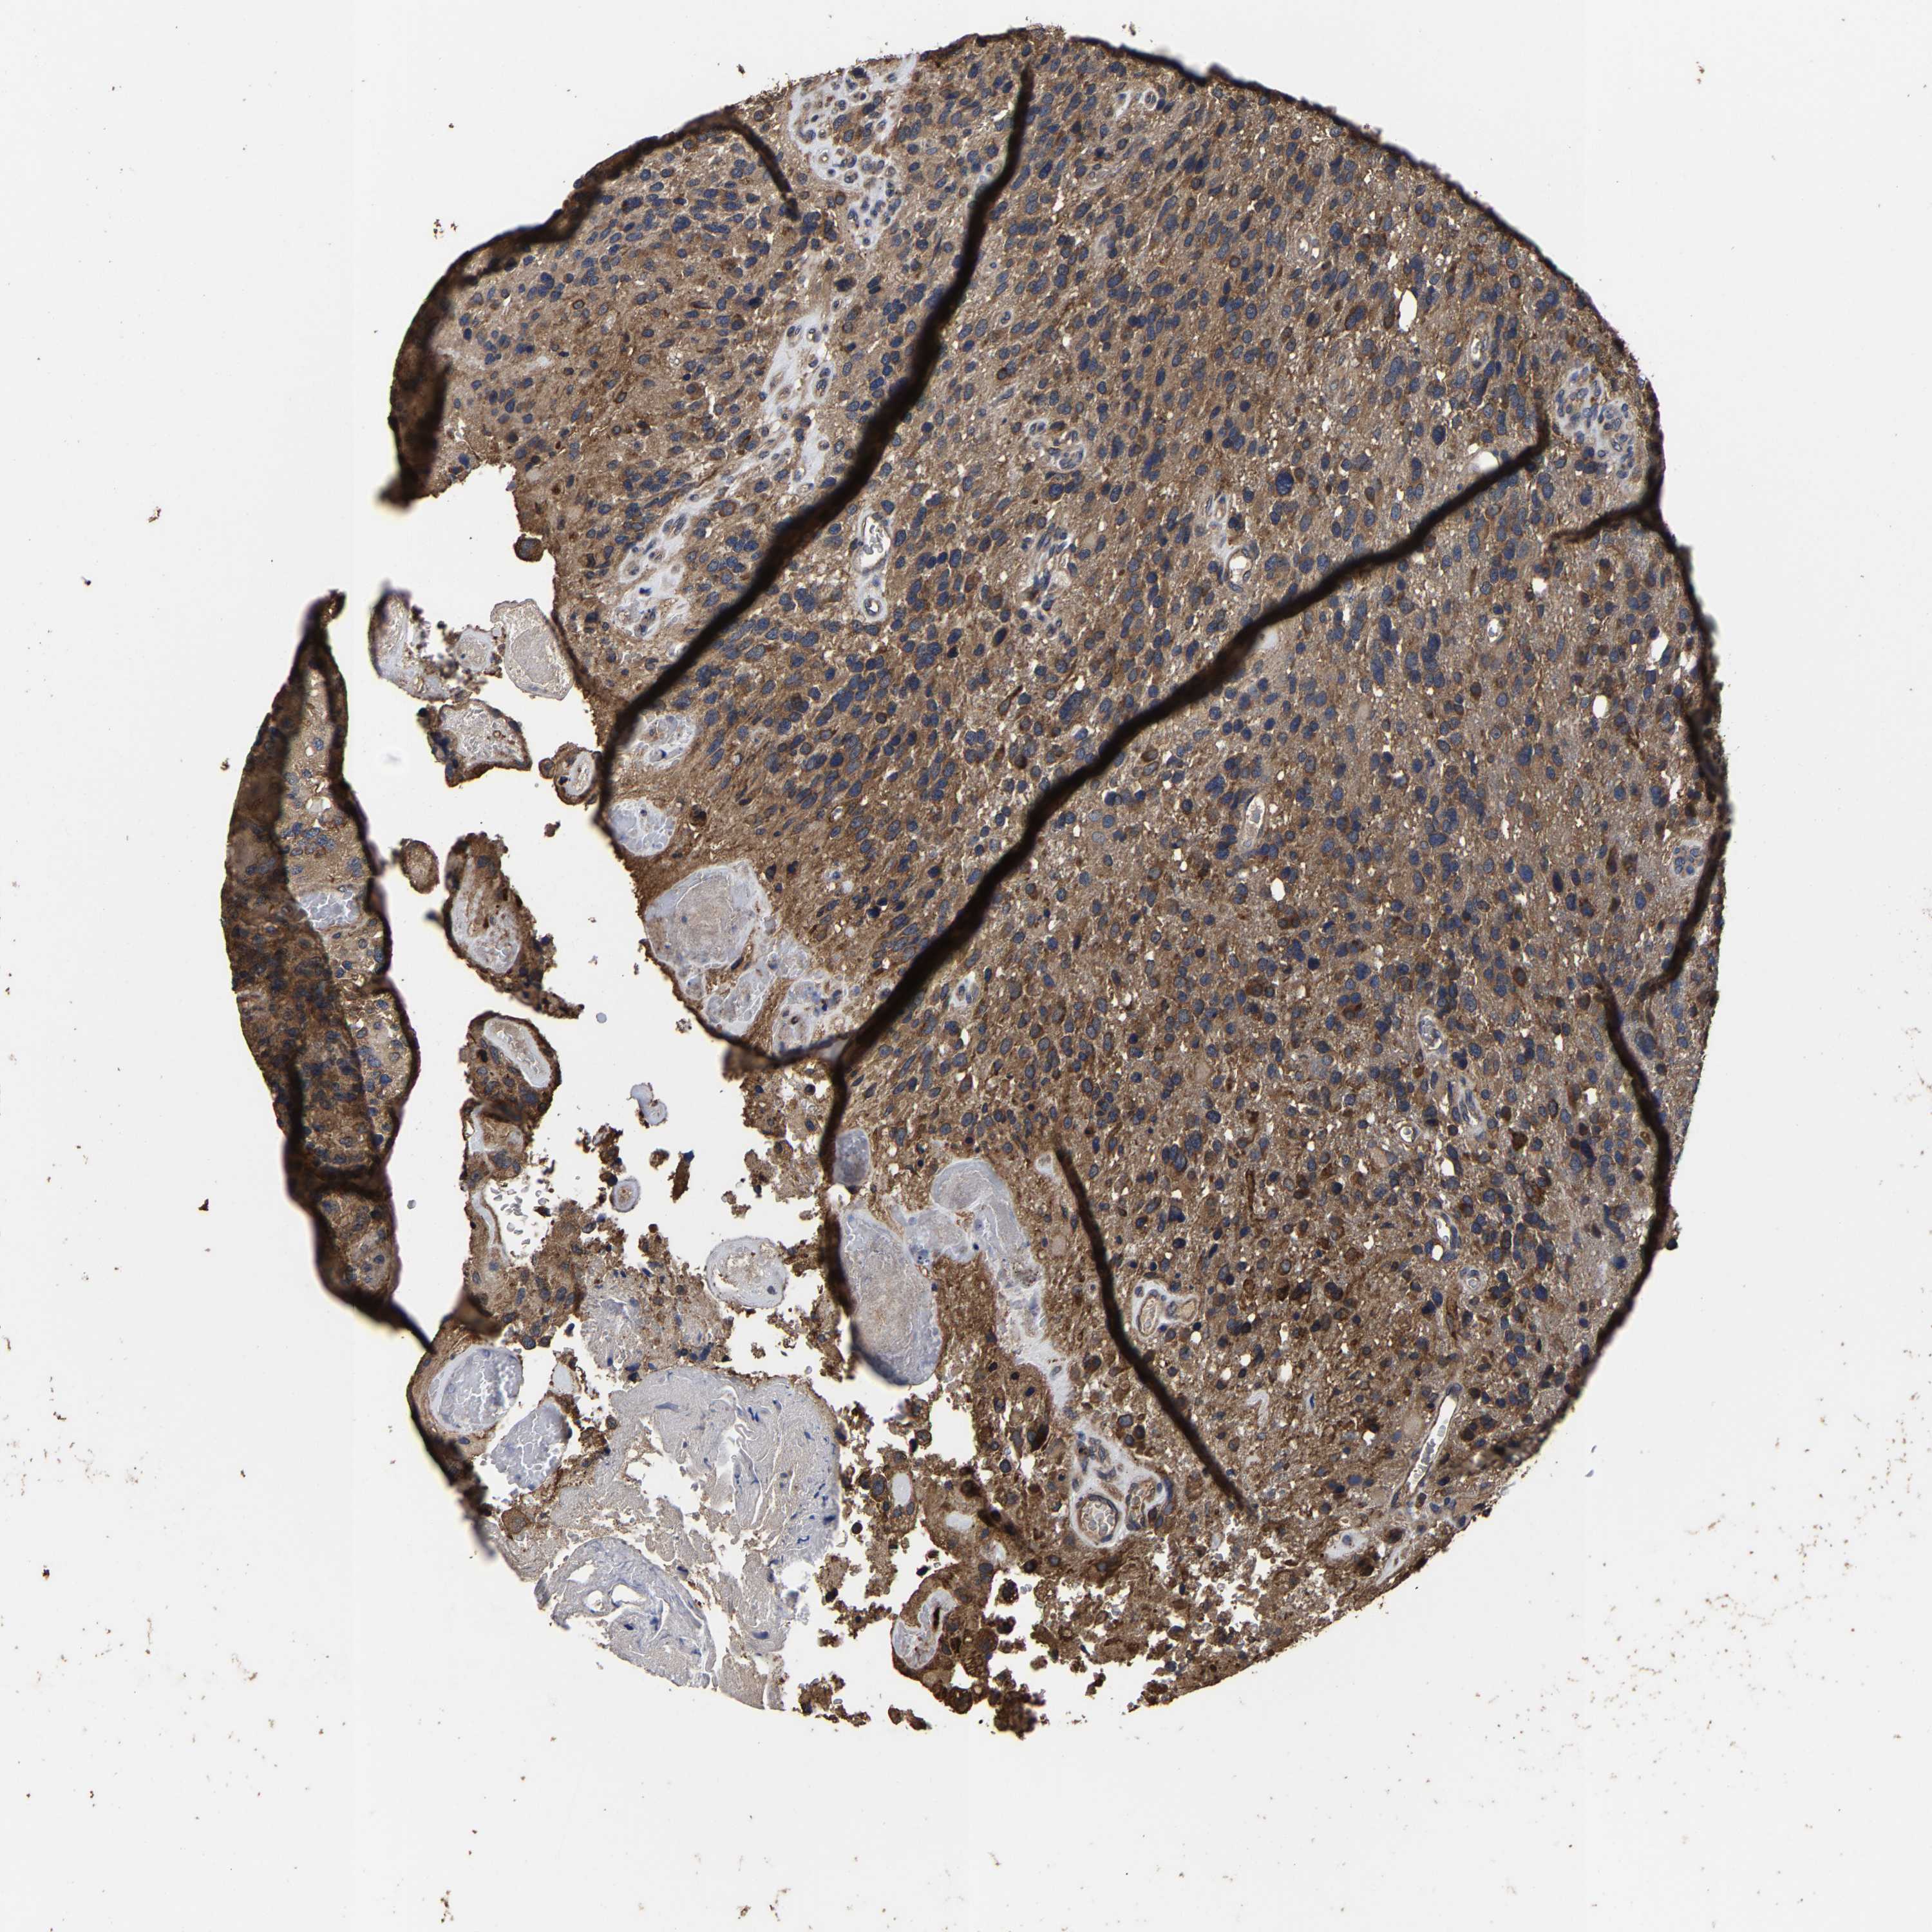

GLIOMA - Protein expressioni

A mouse-over function shows sample information and annotation data. Click on an image to view it in a full screen mode. Samples can be filtered based on level of antibody staining by selecting one or several of the following categories: high, medium, low and not detected. The assay and annotation is described here.

Note that samples used for immunohistochemistry by the Human Protein Atlas do not correspond to samples in the TCGA dataset.

Antibody stainingi

Antibody staining in the annotated cell types in the current human tissue is reported as not detected, low, medium, or high, based on conventional immunohistochemistry profiling in selected tissues. This score is based on the combination of the staining intensity and fraction of stained cells.

Each image is clickable and will lead to virtual microscopy that enables deeper exploration of all samples and also displays staining intensity scores, fraction scores and subcellular localization as well as patient and tissue information for each sample.

Antibody HPA021126

Staining

High

Medium

Low

Not detected

Intensity

Strong

Moderate

Weak

Negative

Quantity

>75%

75%-25%

<25%

None

Location

Nuclear

Cytoplasmic/membranous

Cytoplasmic/membranous,nuclear

Glioma, malignant, High grade

Glioma, malignant, Low grade